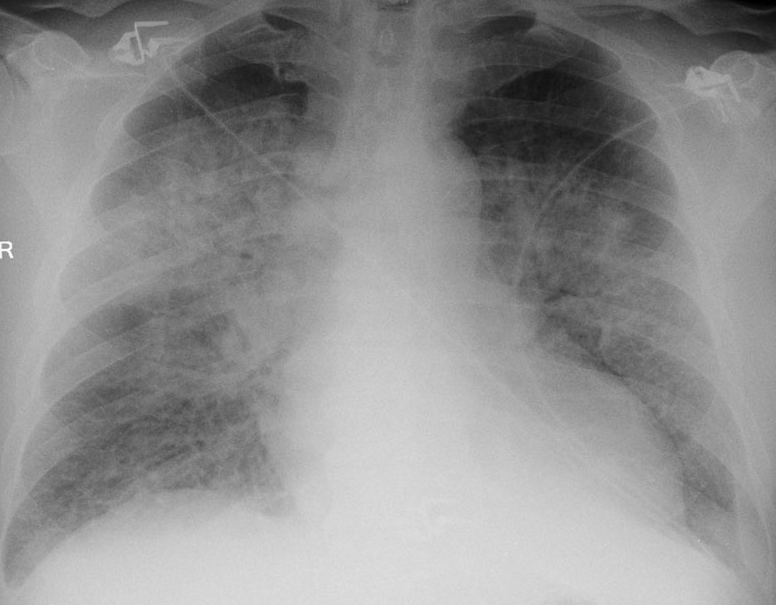

HEART FAILURE CXR